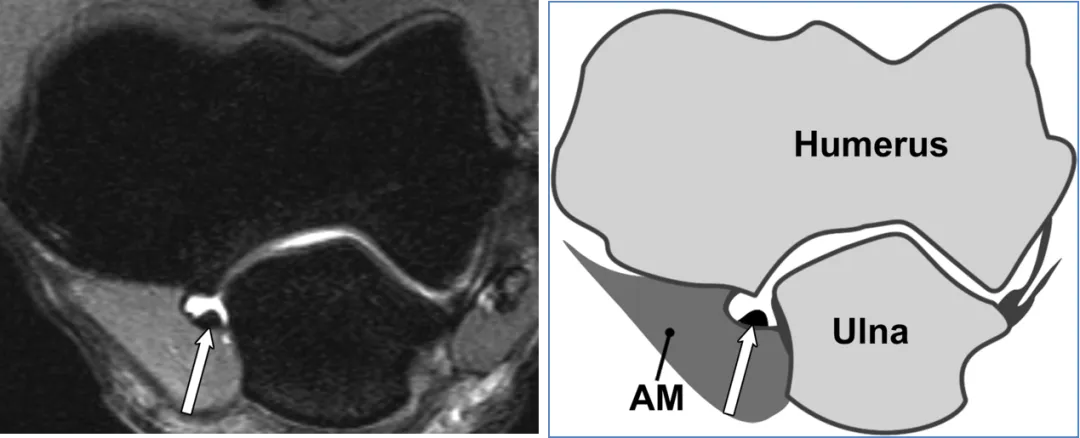

环状韧带(AL)

(a) 40岁男性横轴位中等加权脂肪抑制磁共振成像显示环状韧带与桡骨切迹的后方(白色箭头)和前方(黑色箭头)连接及其绕桡骨头的路径。(b) AL对应示意图显示AL在径向缺口上的后部(白色箭头)和前部(黑色箭头)连接。AM = 无尾肌,BM = 肱肌,BT = 肱肌腱。